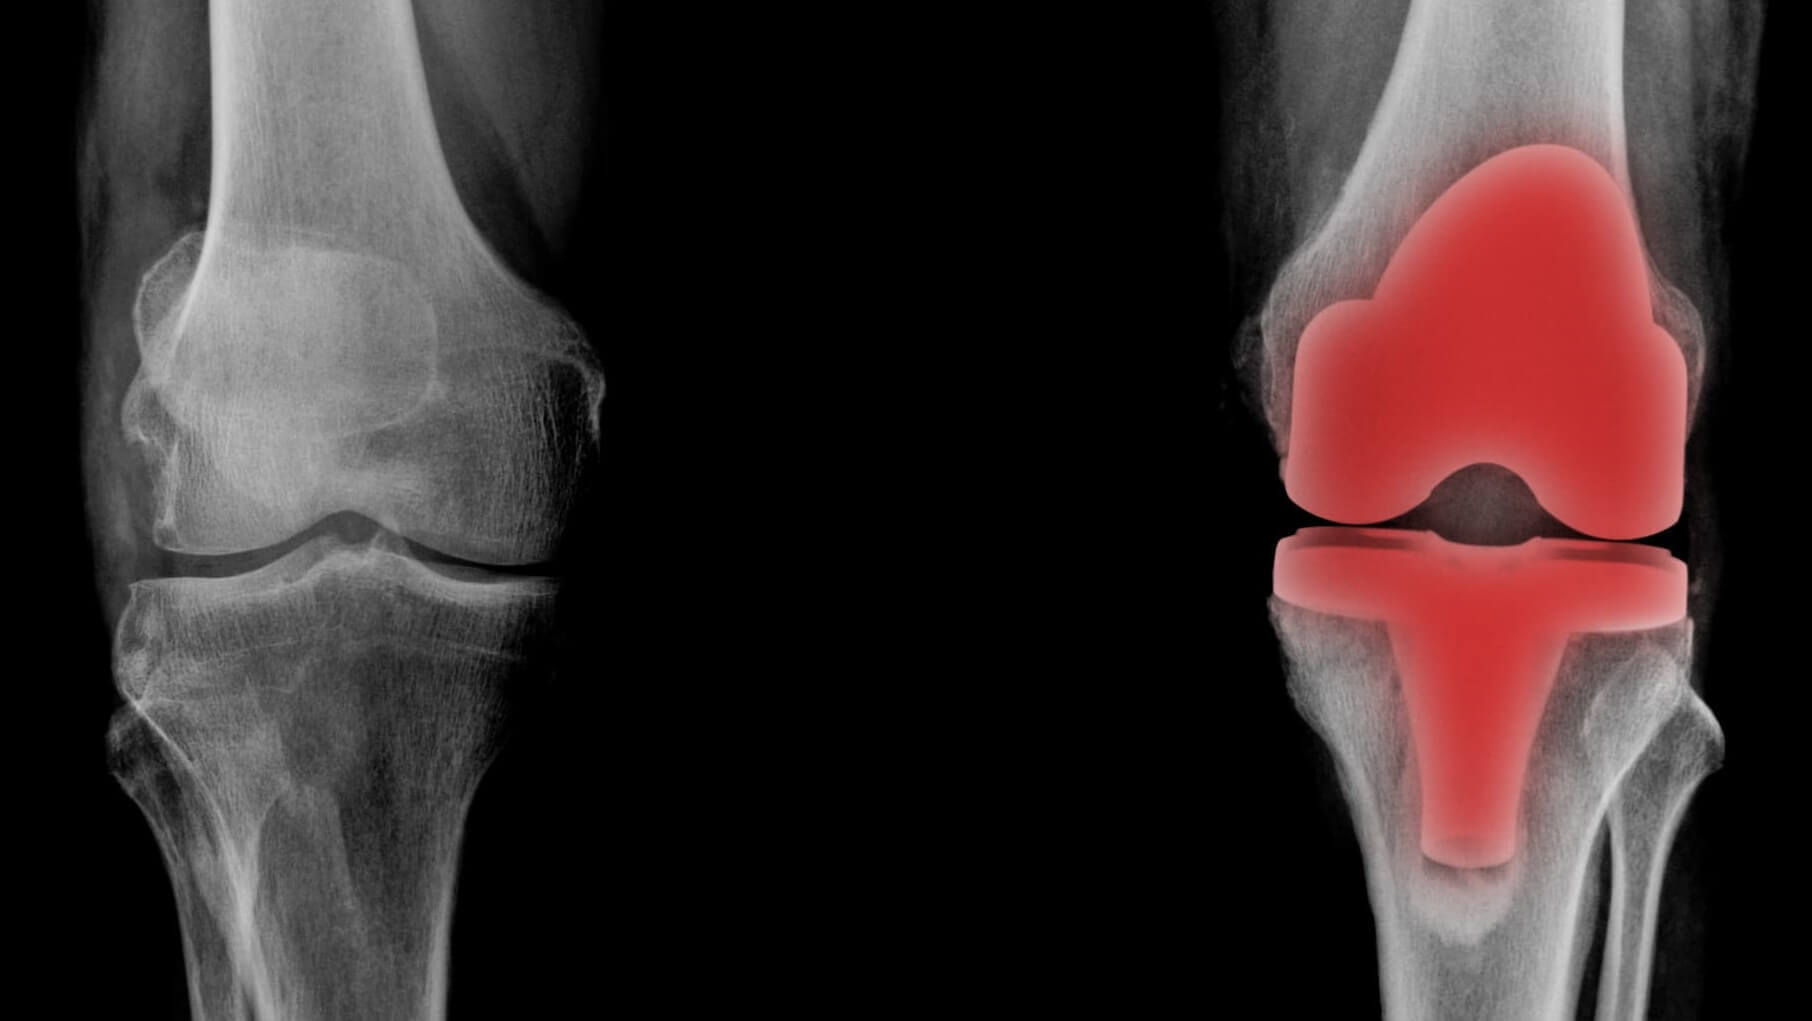

なぜ、病院では「手術しかない」と言われるのか?

整形外科医は、画像診断のスペシャリストです。

レントゲンで

「骨が変形している」 「軟骨がすり減っている」

状態で原因が膝しかないと考えていれば、その結論は原因である膝自体を、

「人工関節に置き換える手術」の一択になります。

しかし、ここに大きな見落としがあります。

人工関節にしても、膝痛が改善しない方が多くおられます。

それは、何故でしょうか?

手術 vs 当院の施術

客観的比較

※ 手術のデータは一般的な脊人工膝関節置換術のものです

手術が必要なケースもあります

以下のような場合は、手術が必要です。

・骨壊死が進行している(大腿骨がギザギザ状態)

・膝が完全に固まって動かない(拘縮)

・症状が急激に悪化している

このようなケースでは、すぐに信頼できる医療機関をご紹介いたします。